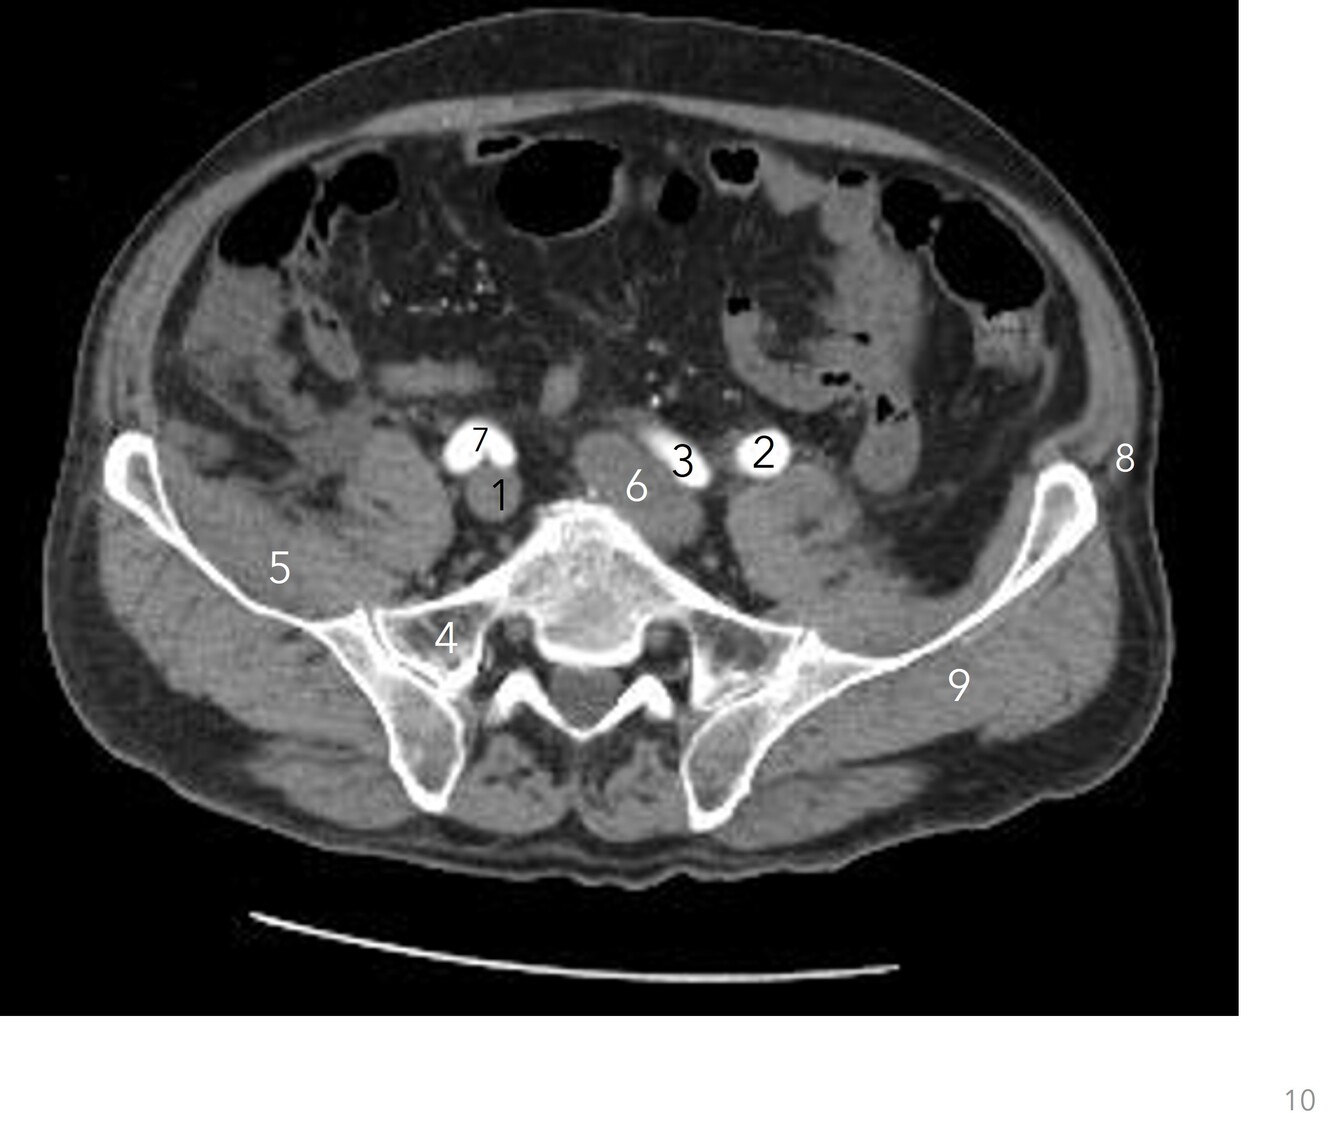

Q

Label 1-7

A

1. Small bowel

2. Lt common iliac artery

3. Lt iliac crest

4. Rt psoas

5. Rt ureter

6. IVC

7. Rt common iliac artery

How well did you know this?

5

1. Lt common iliac artery

2. Rt common iliac artery

3. Lt common iliac vein

4. Rt common iliac vein

5. Ala (Rt ilium)

6. Lt iliacus

7. Lt gluteus medius